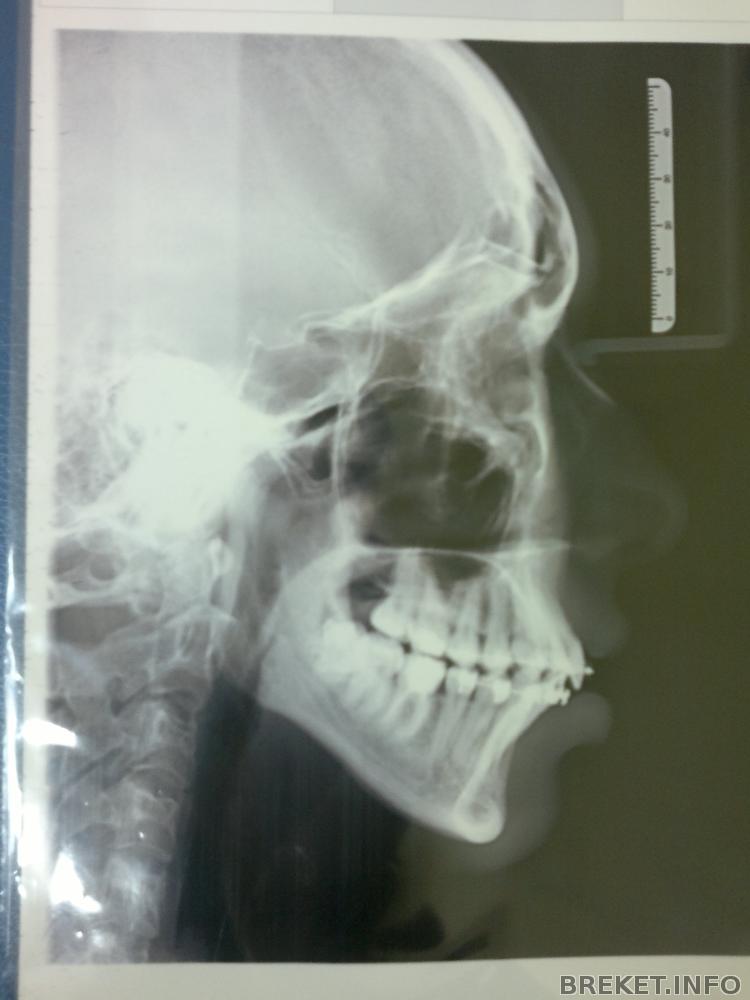

По своим новым "снимочккам" в БС, я определила

(глаз-алмаз) что за год с хвостом, ничего не изменилось

Черепок

И "панорама"